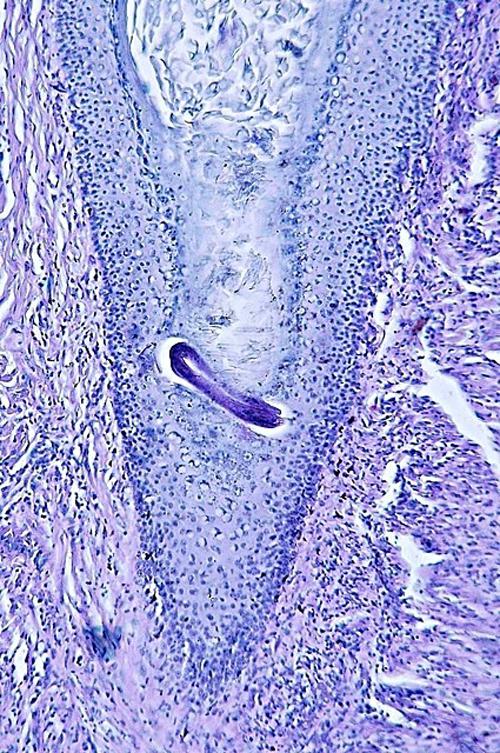

Photo 1 (Hémalun Eosine X 40) peau velue: L’épiderme et les infundibula folliculaires

sont hyperplasiques et hyperkératosiques. Les infundibula folliculaires sont le siège de pustules luminales et

pariétales, avec des fissurations linéaires parallèles au grand axe des follicules.

Le derme montre un inflammation péri-vasculaire et folliculo-centrée à diffuse.

Légendes de la Photo 1 :

- Double flèche bleue pointillée : grand axe des infundibula folliculaires à gaine épithéliale hyperplasique

- Double flèche verte : derme

- Ovales jaunes : pustules dans la paroi des follicules pileux

- Flèches jaunes : fissures linéaires dans la paroi des follicules pileux qui sont parallèles au grand axe des infundibula folliculaires

- Étoiles vertes évidées : lumière d’un follicule pileux hyperkératosique occupée par de la kératine et couche cornée hyperkératosique